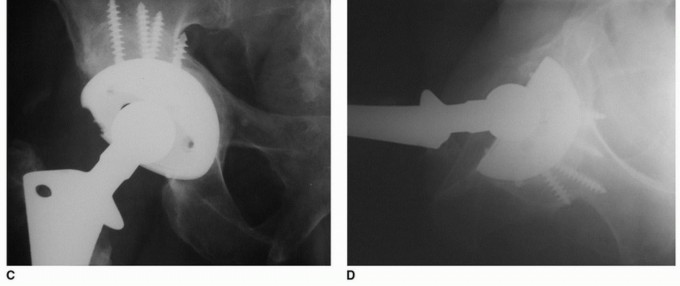

هشاشة العظام حول مفصل الورك الاصطناعي هي تآكل عظمي شائع بعد جراحة استبدال مفصل الورك الكلي، غالبًا بسبب جزيئات البولي إيثيلين. يبدأ العلاج بالتشخيص الدقيق عبر الأشعة المقطعية، ويُعد تبديل بطانة البولي إيثيلين حلاً فعالاً للمكونات الثابتة، مما يقلل الألم ويستعيد وظيفة المفصل بفضل خبرة الأستاذ الدكتور محمد هطيف.

الخلاصة الطبية السريعة: هشاشة العظام حول مفصل الورك الاصطناعي هي تآكل عظمي شائع بعد جراحة استبدال مفصل الورك الكلي، غالبًا بسبب جزيئات البولي إيثيلين. يبدأ العلاج بالتشخيص الدقيق عبر الأشعة المقطعية، ويُعد تبديل بطانة البولي إيثيلين حلاً فعالاً للمكونات الثابتة، مما يقلل الألم ويستعيد وظيفة المفصل بفضل خبرة الأستاذ الدكتور محمد هطيف.

يتناول هذا المقال الأسباب والتشخيص وخيارات العلاج لهشاشة العظام التي تحدث حول مكونات الحُق الثابتة ![توضيح طبي: هشاشة العظام حول مفصل الورك الاصطناعي تبديل بطانة البولي إيثيلين الحل الأمثل](/media/upload/ad023e43-fc70-4c74-a667-a1eb6d8e107d.jpg) ![توضيح طبي: هشاشة العظام حول مفصل الورك الاصطناعي تبديل بطانة البولي إيثيلين الحل الأمثل](/media/upload/e718bae5-3e04-4049-b408-451d4ebed9ed.jpg) ![توضيح طبي: هشاشة العظام حول مفصل الورك الاصطناعي تبديل بطانة البولي إيثيلين الحل الأمثل](/media/upload/436dcac0-c732-444a-8403-539f5c46ae88.jpg) ![توضيح طبي: هشاشة العظام حول مفصل الورك الاصطناعي تبديل بطانة البولي إيثيلين الحل الأمثل](/media/upload/5295a9df-4504-4c8c-89b3-71233cb41476.jpg) ![توضيح طبي: هشاشة العظام حول مفصل الورك الاصطناعي تبديل بطانة البولي إيثيلين الحل الأمثل](/media/upload/c2411af8-be23-4562-90d6-94b6e9d0c0d9.jpg) ![توضيح طبي: هشاشة العظام حول مفصل الورك الاصطناعي تبديل بطانة البولي إيثيلين الحل الأمثل](/media/upload/eda756a8-6677-4b09-b6f5-3619857552e2.jpg) ![توضيح طبي: هشاشة العظام حول مفصل الورك الاصطناعي تبديل بطانة البولي إيثيلين الحل الأمثل](/media/upload/d199b219-f355-4caf-85c3-a764f4913cb3.jpg) ![توضيح طبي: هشاشة العظام حول مفصل الورك الاصطناعي تبديل بطانة البولي إيثيلين الحل الأمثل](/media/upload/ddd6b344-5b51-450e-8239-8e832b923988.jpg) ![توضيح طبي: هشاشة العظام حول مفصل الورك الاصطناعي تبديل بطانة البولي إيثيلين الحل الأمثل](/media/upload/86786efa-0a81-438c-984d-749c462862d5.jpg) ---